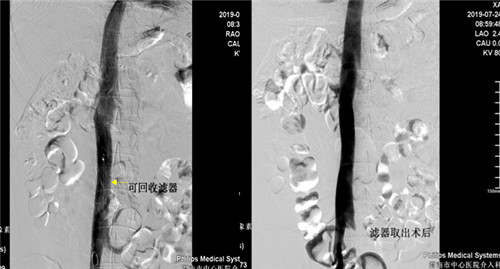

患者是一年轻男性,半年前因高血压性脑出血住院治疗,发现左下肢髂静脉股静脉腘静脉胫后胫前静脉血栓形成,由于脑出血有抗凝溶栓禁忌症,为预防肺栓塞的发生急诊行下腔静脉滤器(可回收)植入术,患者无脑出血后进行规范抗凝再无出血,超声复查下肢静脉血管未见新鲜血栓,D-二聚体正常,于7月24日早八点行经颈静脉下腔静脉滤器取出术,术后患者无腹痛发热出血等症状。

目前市中心医院对于下肢深静脉血栓形成患者常采用DENALI可回收下腔静脉滤器(最长回收时间窗632天)置入术预防肺栓塞的发生,该手术已在乐鱼手机站入口广泛开展。但下腔静脉滤器取出术在渭南区域内尚未开展,市中心医院首次成功取出DENALI可回收下腔静脉滤器,标志着因担心滤器永久置入发生并发症而纠结放与不放的时代已结束,亦开创了渭南市血管介入新篇章,更好地为各科室的临床工作保驾护航,为更多的患者带来福音。